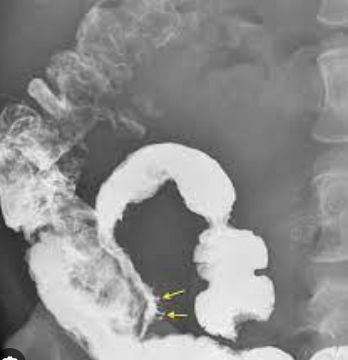

What sign of Crohn’s Disease are the arrows pointing to? [1]

Rosehorn ulcer